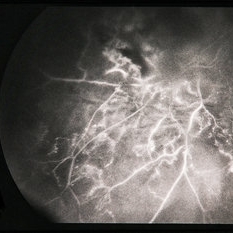

BRVO - Massive Exudate from Collaterals

Feb 24 2014 by David Callanan, MD

66-year-old female with BRVO - massive exudate from collaterals, 20/70 OD; 20/25 OS in 1985; +HTN, glaucoma; 20/200 OD 1987.

Condition/keywords: branch retinal vein occlusion (BRVO), collaterals, exudate